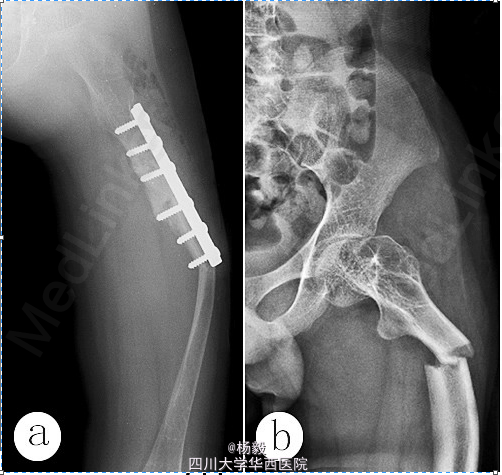

患者,男,7岁时因跌倒致左股骨中上段骨折于2004-06-26入院,行复位钢板内固定,4个月后骨折端愈合。13岁时因左大腿和右小腿逐渐出现弓形畸形、肢短、跛行3年于2011-09-07入院

;查体:明显跛行步态,左大腿中上段和右小腿中段向前呈弓形畸形,左小腿中段轻度呈弓形畸形,左下肢较右下肢短6cm;X线片示左股骨中上段和右胫腓骨中段明显呈弓形,左胫腓骨中段呈轻度弓形(图1a、b、c),股骨和胫骨骨皮质菲薄;

行左股骨中上段和右胫骨中段截骨矫形钢板内固定术,因第一次股骨钢板固定后钢板远端出现股骨骨折,所以更换长钢板固定;因左胫腓骨中段骨质脆,骨皮质极薄,未行截骨矫形术